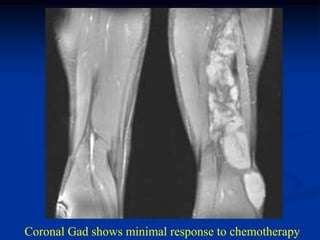

Coronal Gad shows minimal response to chemotherapy

Coronal Gad showsminimal response to chemotherapy